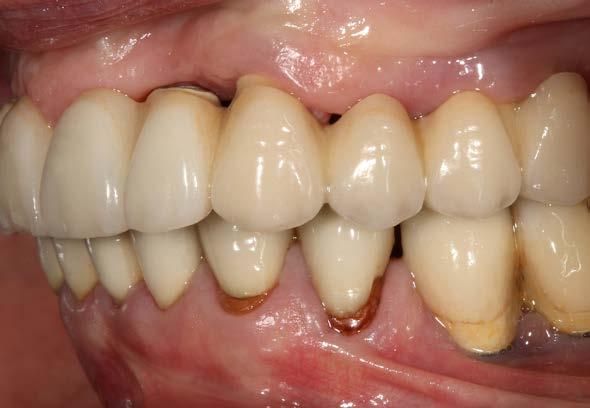

Figuras 2 y 3. Imágenes intraorales de la paciente, donde podemos observar la pérdida ósea acusada en algunos puntos con exposición de los componentes protésicos, así como transparencia incluso de las espiras de los implantes como el situado en posición 13 a través del tejido gingival.